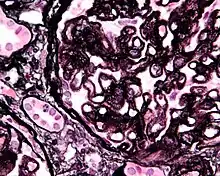

Renal corpuscle (glomerulus) showing glomular basement membrane.